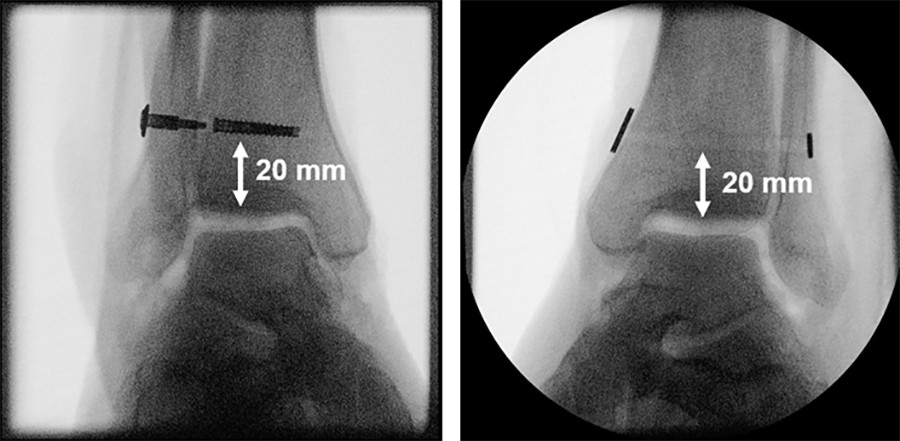

Eight pairs of human anatomical specimens, namely lower legs, were scanned by computed tomography (CT) under 700 N single-leg axial loading in five foot positions – neutral, 15° external/internal rotation and 20° dorsiflexion/plantarflexion in three different states: (1) pre-injury (intact); (2) injured, characterized by complete syndesmosis and deltoid ligaments cuts simulating pronation-eversion injury types III and IV as well as supination-eversion injury type IV according to Lauge-Hansen; (3) reconstructed, using a screw-suture (FIBULINK, Group 1) or a suture-button (TightRope, Group 2) implant for syndesmotic stabilization, placed 20 mm proximal to the tibia plafond/joint surface (Fig 2).